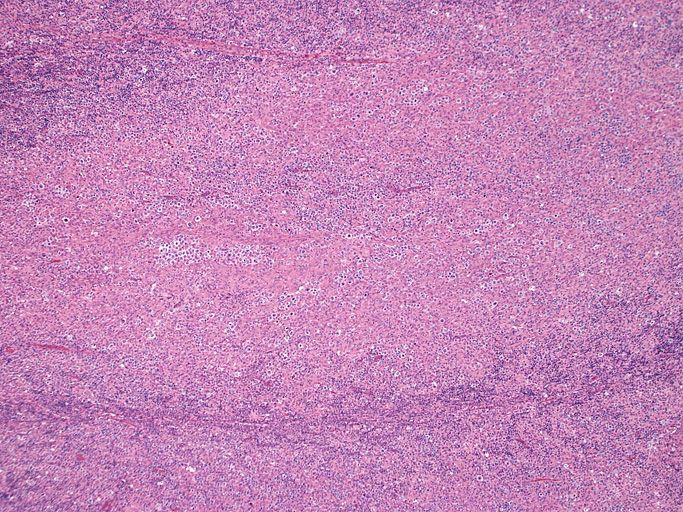

直径17mmの腫大したリンパ節。被膜は軽度線維性肥厚を示す。リンパ節の基本構造は失われ不明瞭な結節様構造が集蔟しているように見える。

光顕および免疫染色所見

結節構造内では, 好酸性細胞質をもつ組織球の増生を背景に大型異型細胞が散在性または集蔟して増殖している。被膜下にも線維化組織内にbizzarreな大型細胞が認められる。リンパ球は小型リンパ球が大型異型細胞を含む組織球性の結節辺縁に存在する。大型細胞は, centroblastic cellが多く, その他 Hodgkin cell-like cell, RS細胞様巨細胞, 腎臓型の核をもった細胞, 多型核の細胞など多彩な形態を示す。異型核分裂像をふくむ核分裂像が多い。